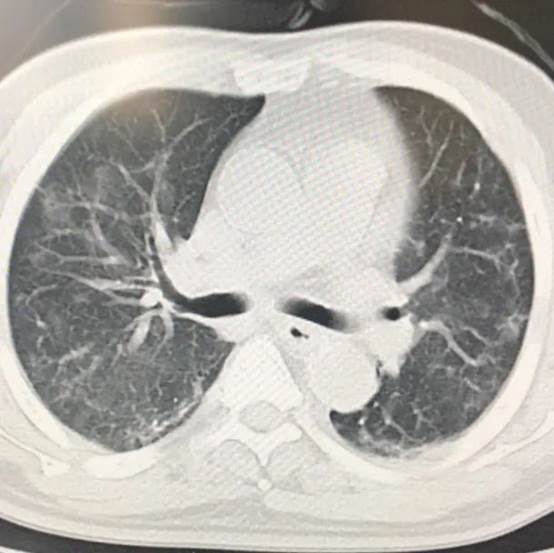

2月7日 CT影像

1月31日,老吕各项指标好转,顺利转出重症监护室。